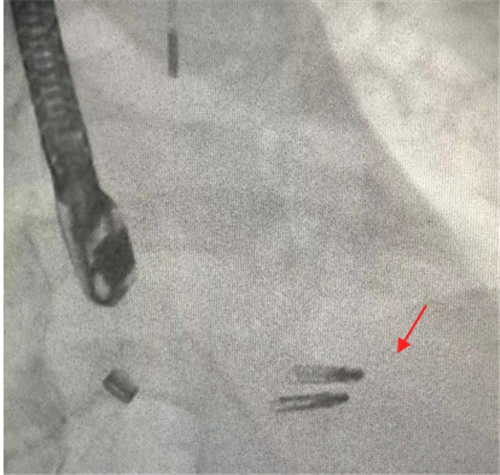

术中使用二枚二尖瓣钳子完成手术

2月2日上午,贺先生在全麻下进行介入手术。经手术团队充分缜密的术前准备,成功为患者植入2个二尖瓣夹。术后患者反流情况明显改善,跨瓣平均压差4mmHg,左上和右上肺静脉逆流明显改善,反流改善明显。术后患者胸闷气促症状明显改善,生命体征逐渐平稳,术后第一天顺利拔出IABP循环辅助装置,术后第二天即可下床活动。贺先生出院当日,热泪盈眶地说:“我以为这个年跨不过去了,感谢你们给了我第二次生命,让我重获新生,可以回家过年了。”